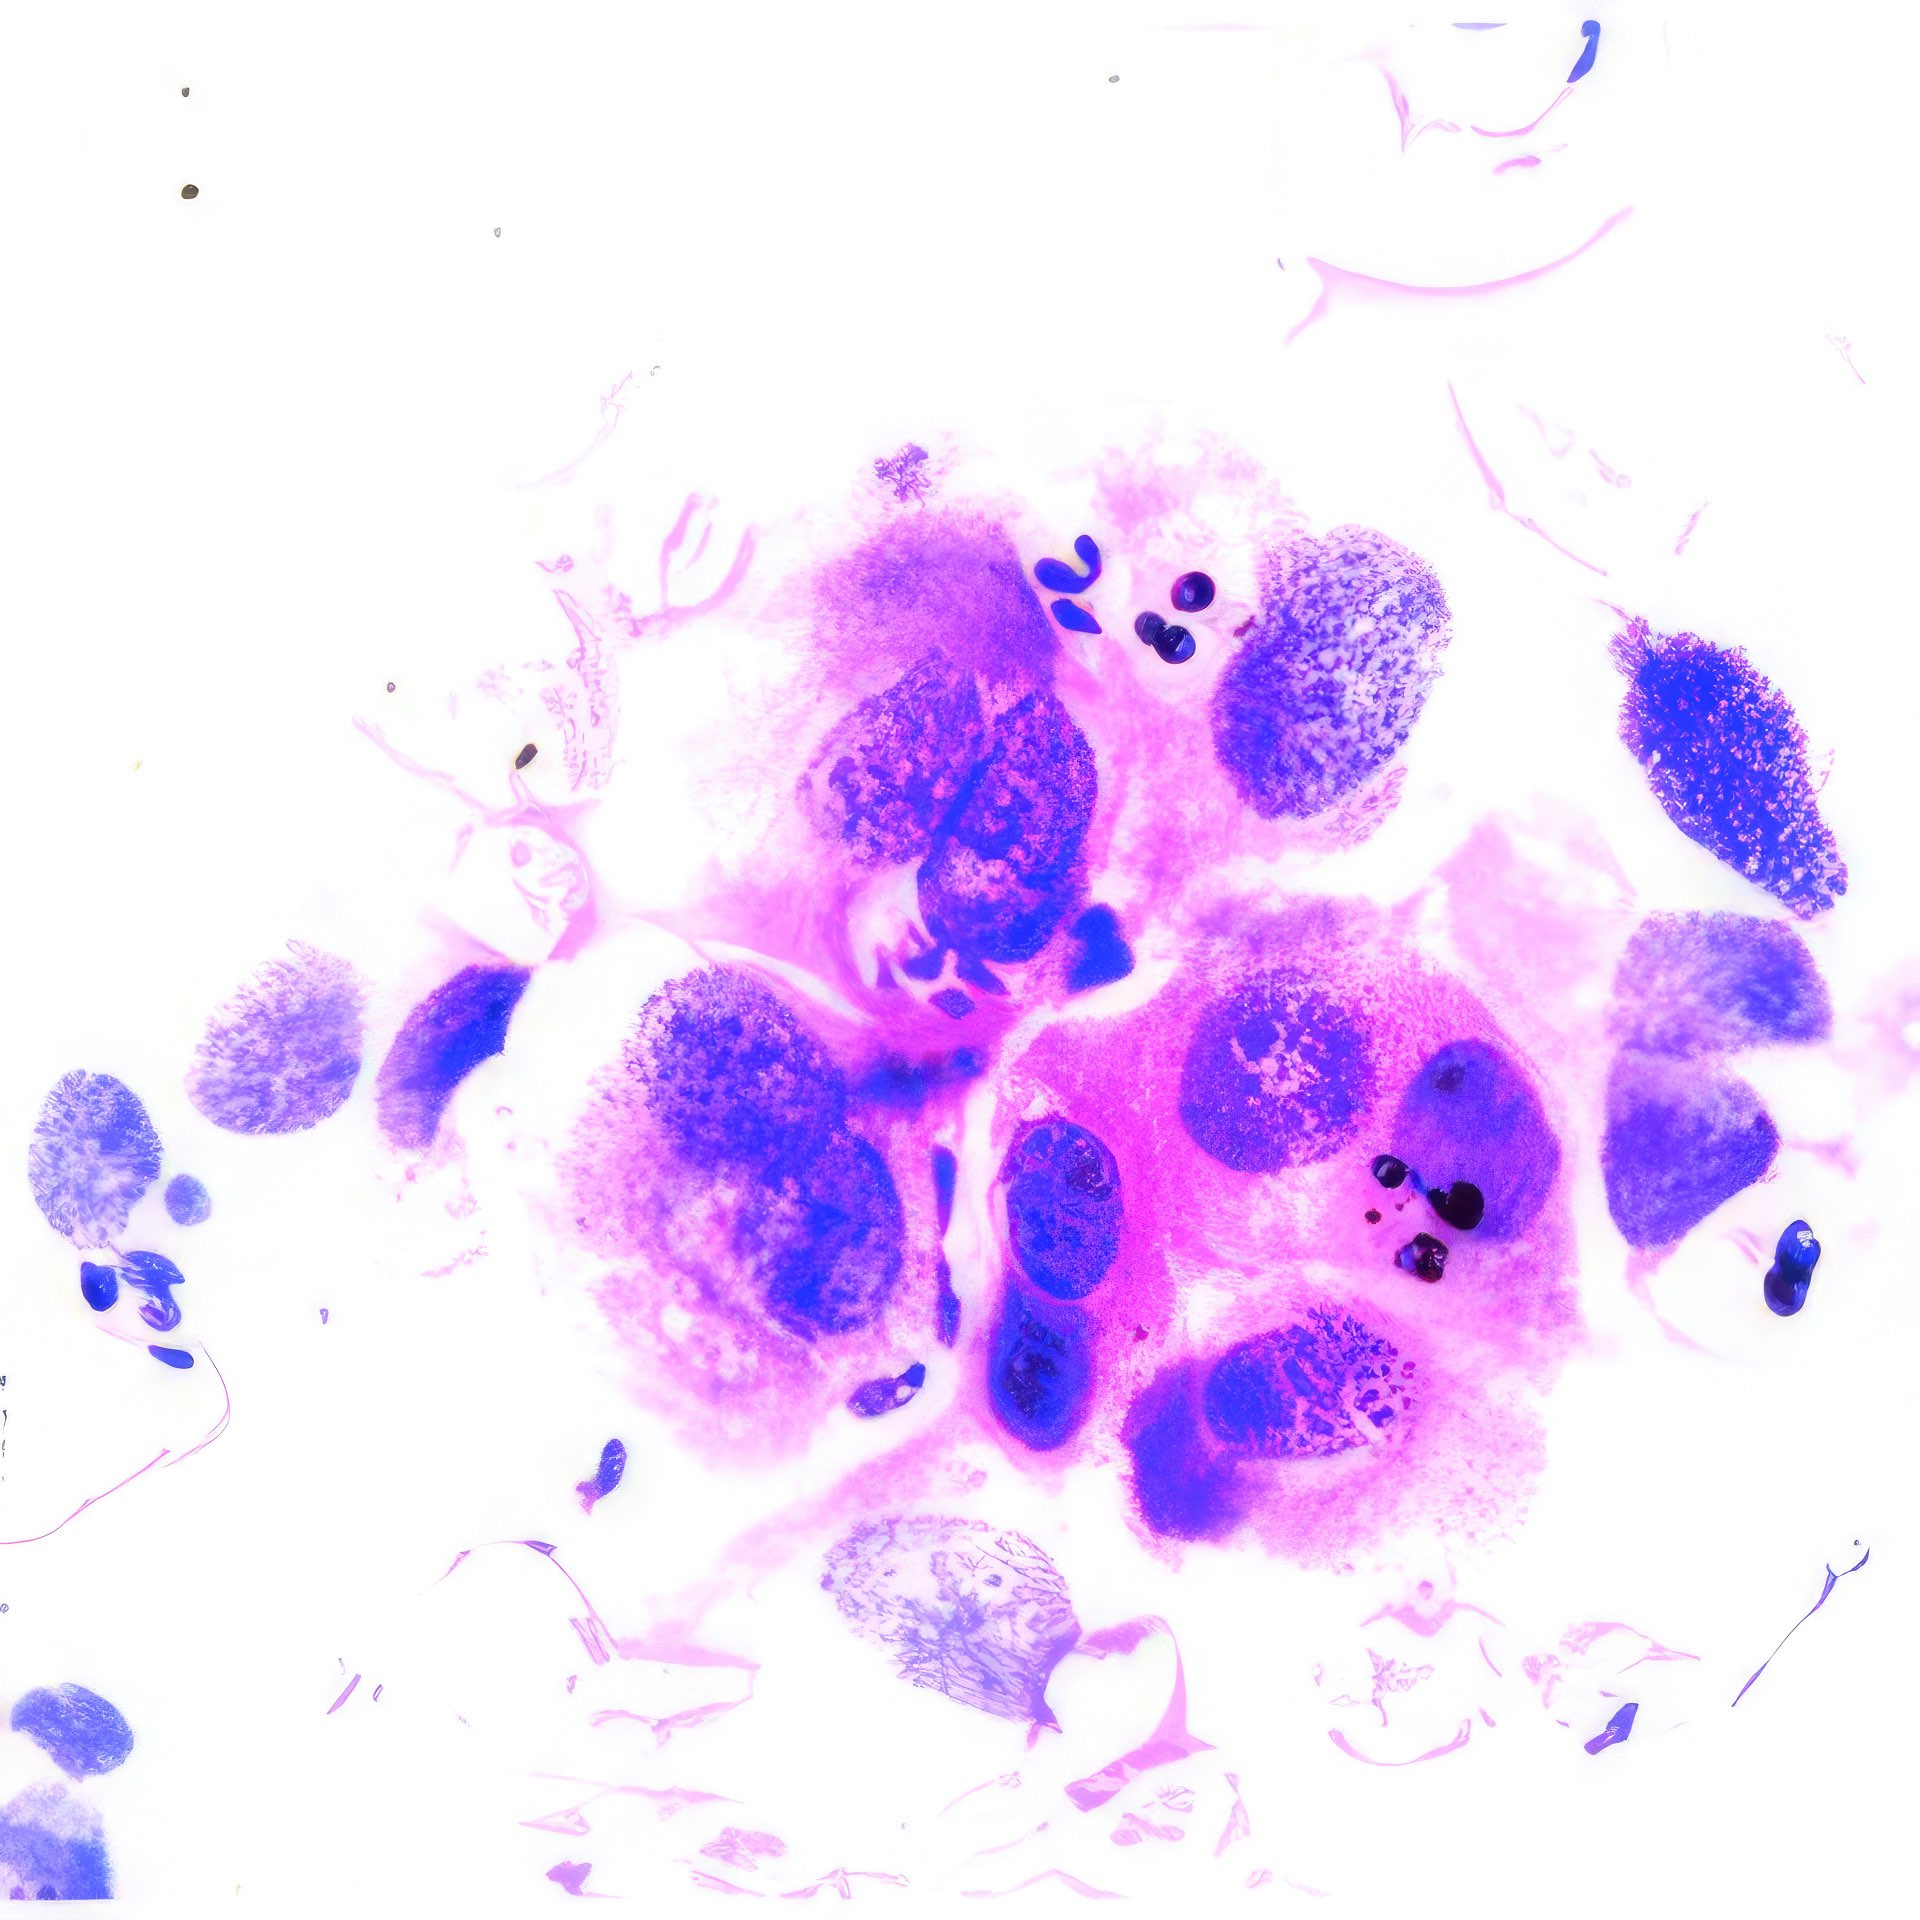

Frau, 60 Jahre

Linkes Brustödem mit Veränderung der areolären Haut seit 3 Jahren,

axilläre Lymphadenopathie und linkes Handödem seit 2 Monaten.

(Abbildungen 3 - 6: Pap, Vergrößerung 1000x)

Makroskopisch zeigt die areoläre Haut (Brustwarzenhof) eine feine ekzemartige nässende granuläre Struktur; die Brustwarze ist nicht eingezogen (Abb. 1 und 2). Die extrem atypischen Zellen liegen verstreut (Abb. 3), oder bilden lose zusammenhängende Gruppen (Abb. 4, 6). Einige sind doppelkernig. Im Vergleich zum gewöhnlichen Mammakarzinom sind sie extrem pleomorph und ihre Kerne sind stärker hyperchromatisch, sehr grob strukturiert, und zeigen manchmal prominente Chromozentren. Das Zytoplasma ist unterschiedlich breit und erscheint manchmal als vakuolär.

Histologie

Das durch Stanzbiopsie gewonnene histologische Präparat zeigt viele große, scheinbar vakuolisierte Zellen innerhalb des Plattenepithels. Eine PAS-Färbung war nicht möglich.

Die zytologischen und histologischen Befunde sind charakteristisch für das Paget-Syndrom. Histologisch würden die Zellen PAS-positiv sein. Das Brustödem, die nicht eingezogene Brustwarze und die axilläre Schwellung weisen auf ein tiefsitzendes Karzinom hin, das bereits in die axillären Lymphknoten metastasiert hat. Die Kombination von Karzinom und Morbus Paget ist nicht ungewöhnlich 1. - Die extrem atypischen Zellen können zu einer Verwechslung mit einem Plattenepithelkarzinom führen 2. Andererseits unterscheidet dies die Zellen des Morbus Paget von denen des Adenoms, das ebenfalls in der areolären Region auftritt 3, 4. Schließlich können die makroskopisch erscheinenden vesikulären Strukturen einen Pemphigus vulgaris, eine Autoimmunerkrankung der Haut, simulieren 5.